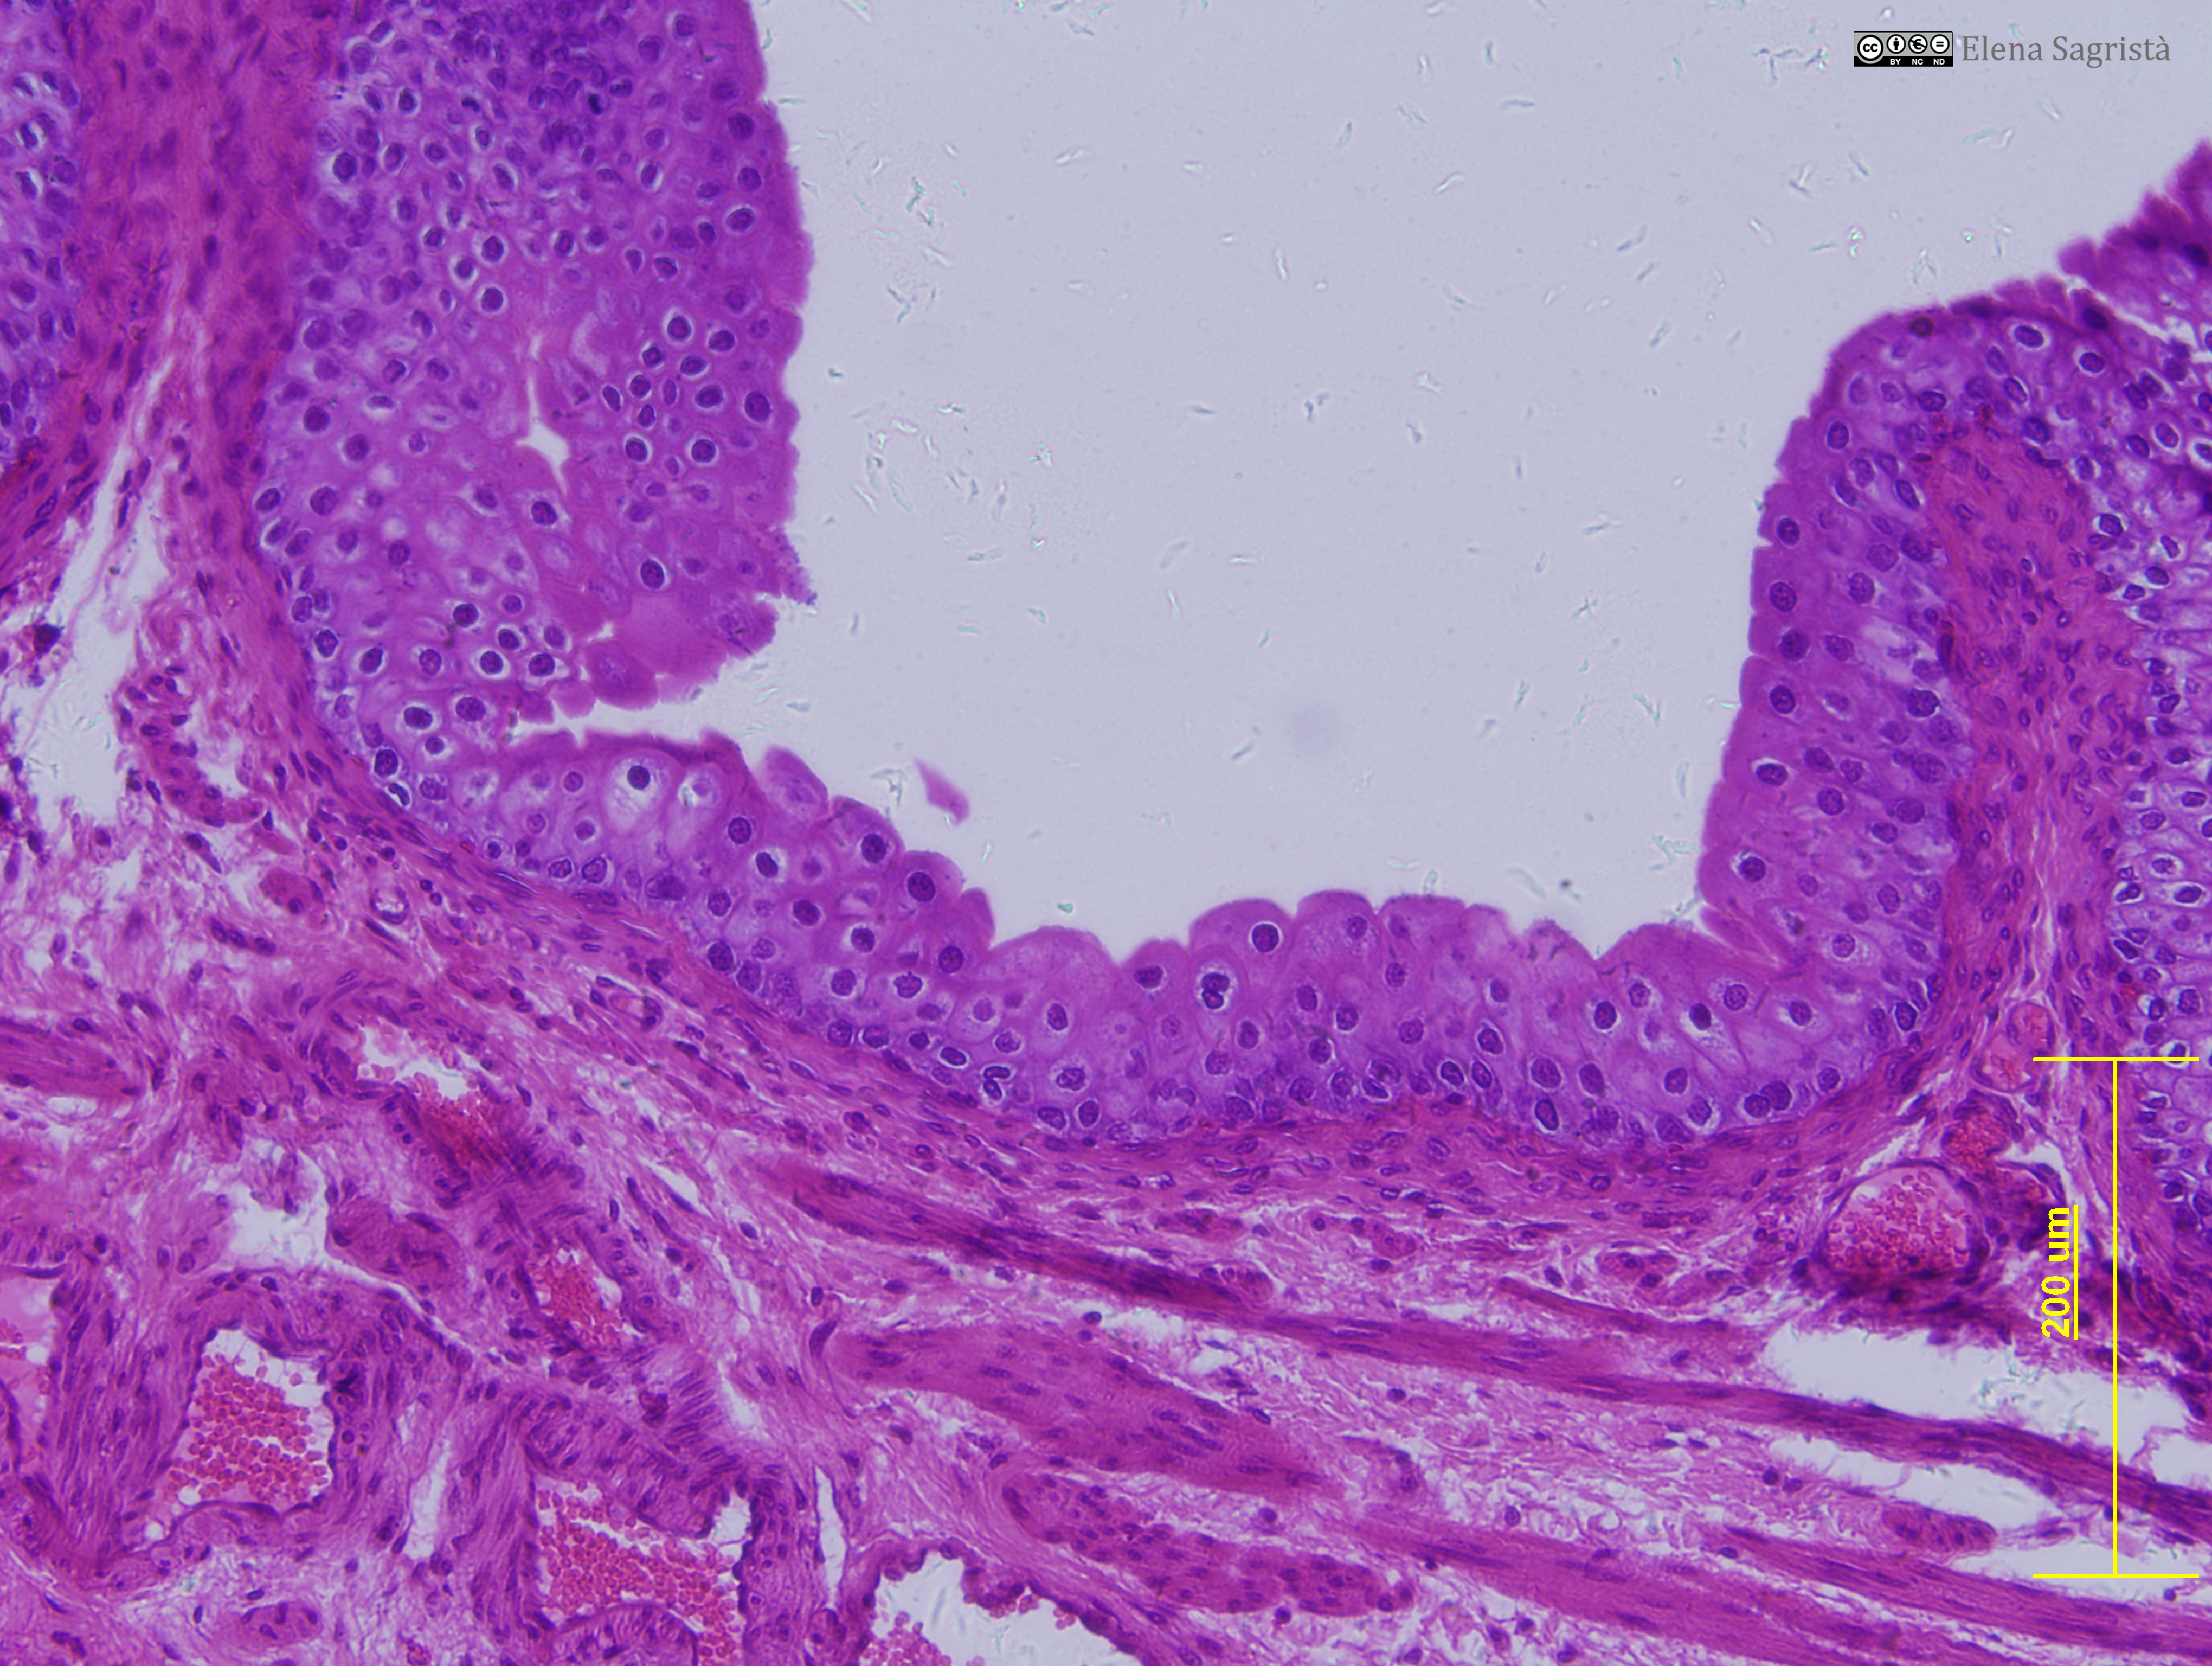

Histologia imatges: 01 Teixit epitelial

Imatges de preparacions histològiques de teixit epitelial. Microscopia òptica.